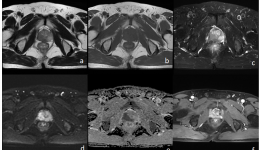

近日,我院放射科新开展了一例盆腔MRI扫描——前列腺MR扫描,下面我们来看看这个例子吧。患者男72岁反复肛门部坠胀、便不尽感3+月。4月6-7日前列腺MRIa-c:前列腺右侧份(以外周带为主)T1WI斑片状等低信号影,T2WI低信号影d-e:病灶DWI上呈高信号...